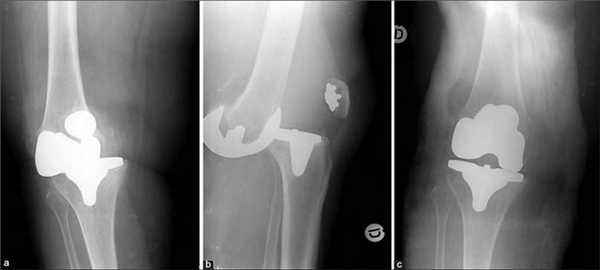

Замена коленного сустава (ЗКС) - метод хирургического лечения последствий дегенеративно-дистрофического патогенеза колена. Цель операции полное восстановление функций проблемного отдела конечности за счет замены необратимо пораженного сочленения эндопротезом. Гонартроз 3-й степени (в 85% случаев) самая частая причина.

Артроз коленного сустава на рентгене.

Показания к замене

Посмотрите на рентген, на нем вы видите, до какой степени при запущенном гонартрозе изношен гиалиновый хрящ, обеспечивающий гладкое скольжение суставных поверхностей. Концевые участки костей грубо деформируются нарушая функции сгибания и разгибания конечности вызывая интенсивный болевой синдром.

Две техники операции у одного пациента.

Одномыщелковая замена сустава на рентгене.

Сравнение двух типов операций.